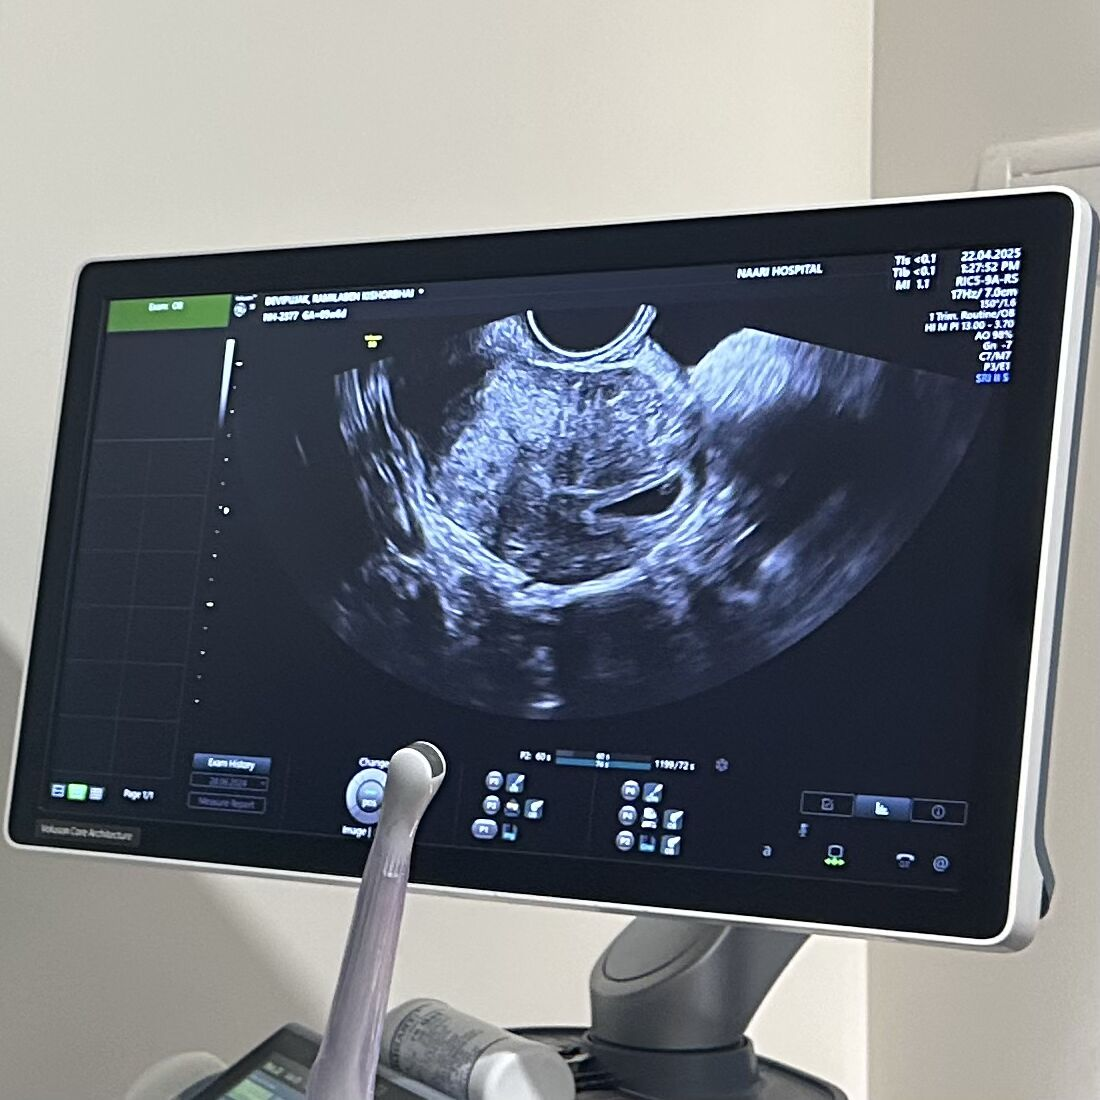

A brave woman recently achieved pregnancy after undergoing IVF treatment at Naari Hospital, which at one stage seemed impossible.

And then… she conceived in her second IVF attempt!